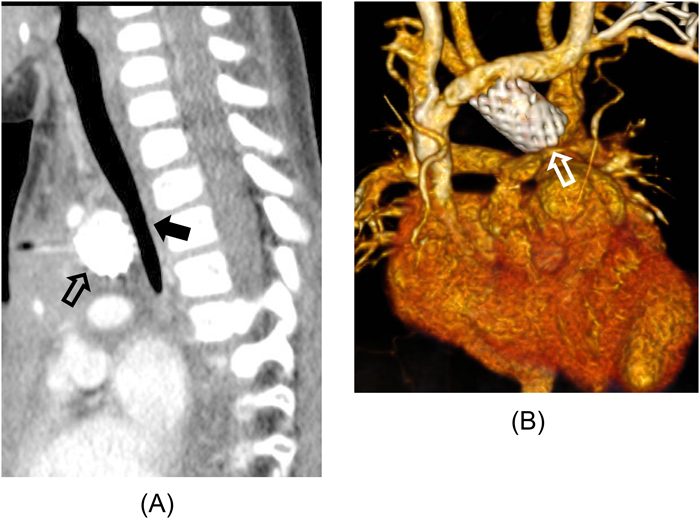

感染性腕頭動脈瘤に対してカバードステント留置術を行った乳児例An Infantile Case of Covered Stent Implantation for Infectious Aneurysms of the Brachiocephalic Artery